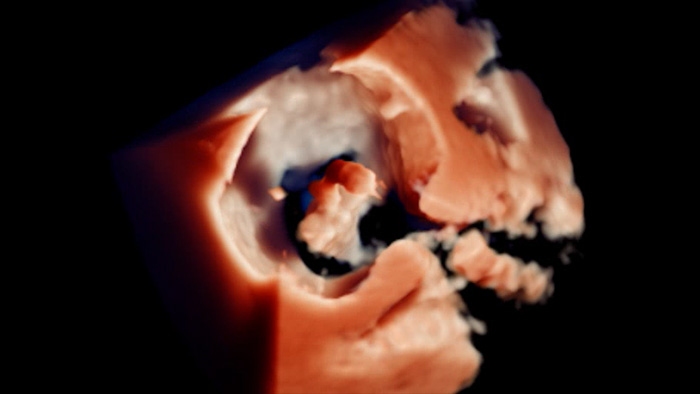

Visualización de la reparación mitral de la regurgitación posimplante

Visualización TrueVue de la valvulopatía mitral de extremo a extremo